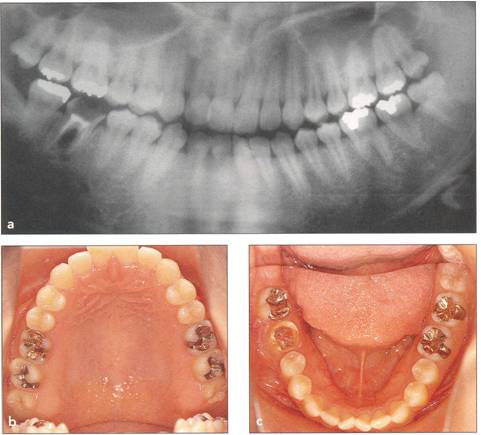

Fi 545e45f g 5-1a Preoperative panoramic view. The patient is a 24-year-old female. Transplantation of the mandibular right third molar to the area of nonrestorable mandibular first molar is planned. |

Fi 545e45f gs 5-1b and 5-1c Maxillary and mandibular teeth after initial periodontal treatment of brushing, scaling, and root planing. |

Fi 545e45f g 5-1d Preoperative periapical radiograph. |

Fi 545e45f g 5-1e Preoperative view of the donor tooth and the recipient site. |